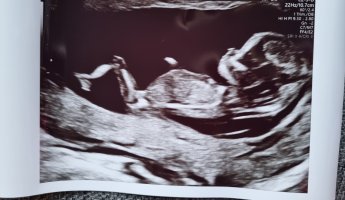

12+3 (målt til 12+5 idag)

Vi har en bebis perfektus på vei! Alt så helt perfekt ut, Lille var veldig aktiv, vinket, sprellet, strakk seg ut. Legen kalte den skihopper

Jeg kunne sett på den i evigheter, og vi fikk med oss ni bilder! Nå er alt verdt det. All kvalme, all smerte, all bekymring, alt er blåst vekk! Fin nakkefold, fin nese, ti små fingre, perfekte små armer og bein